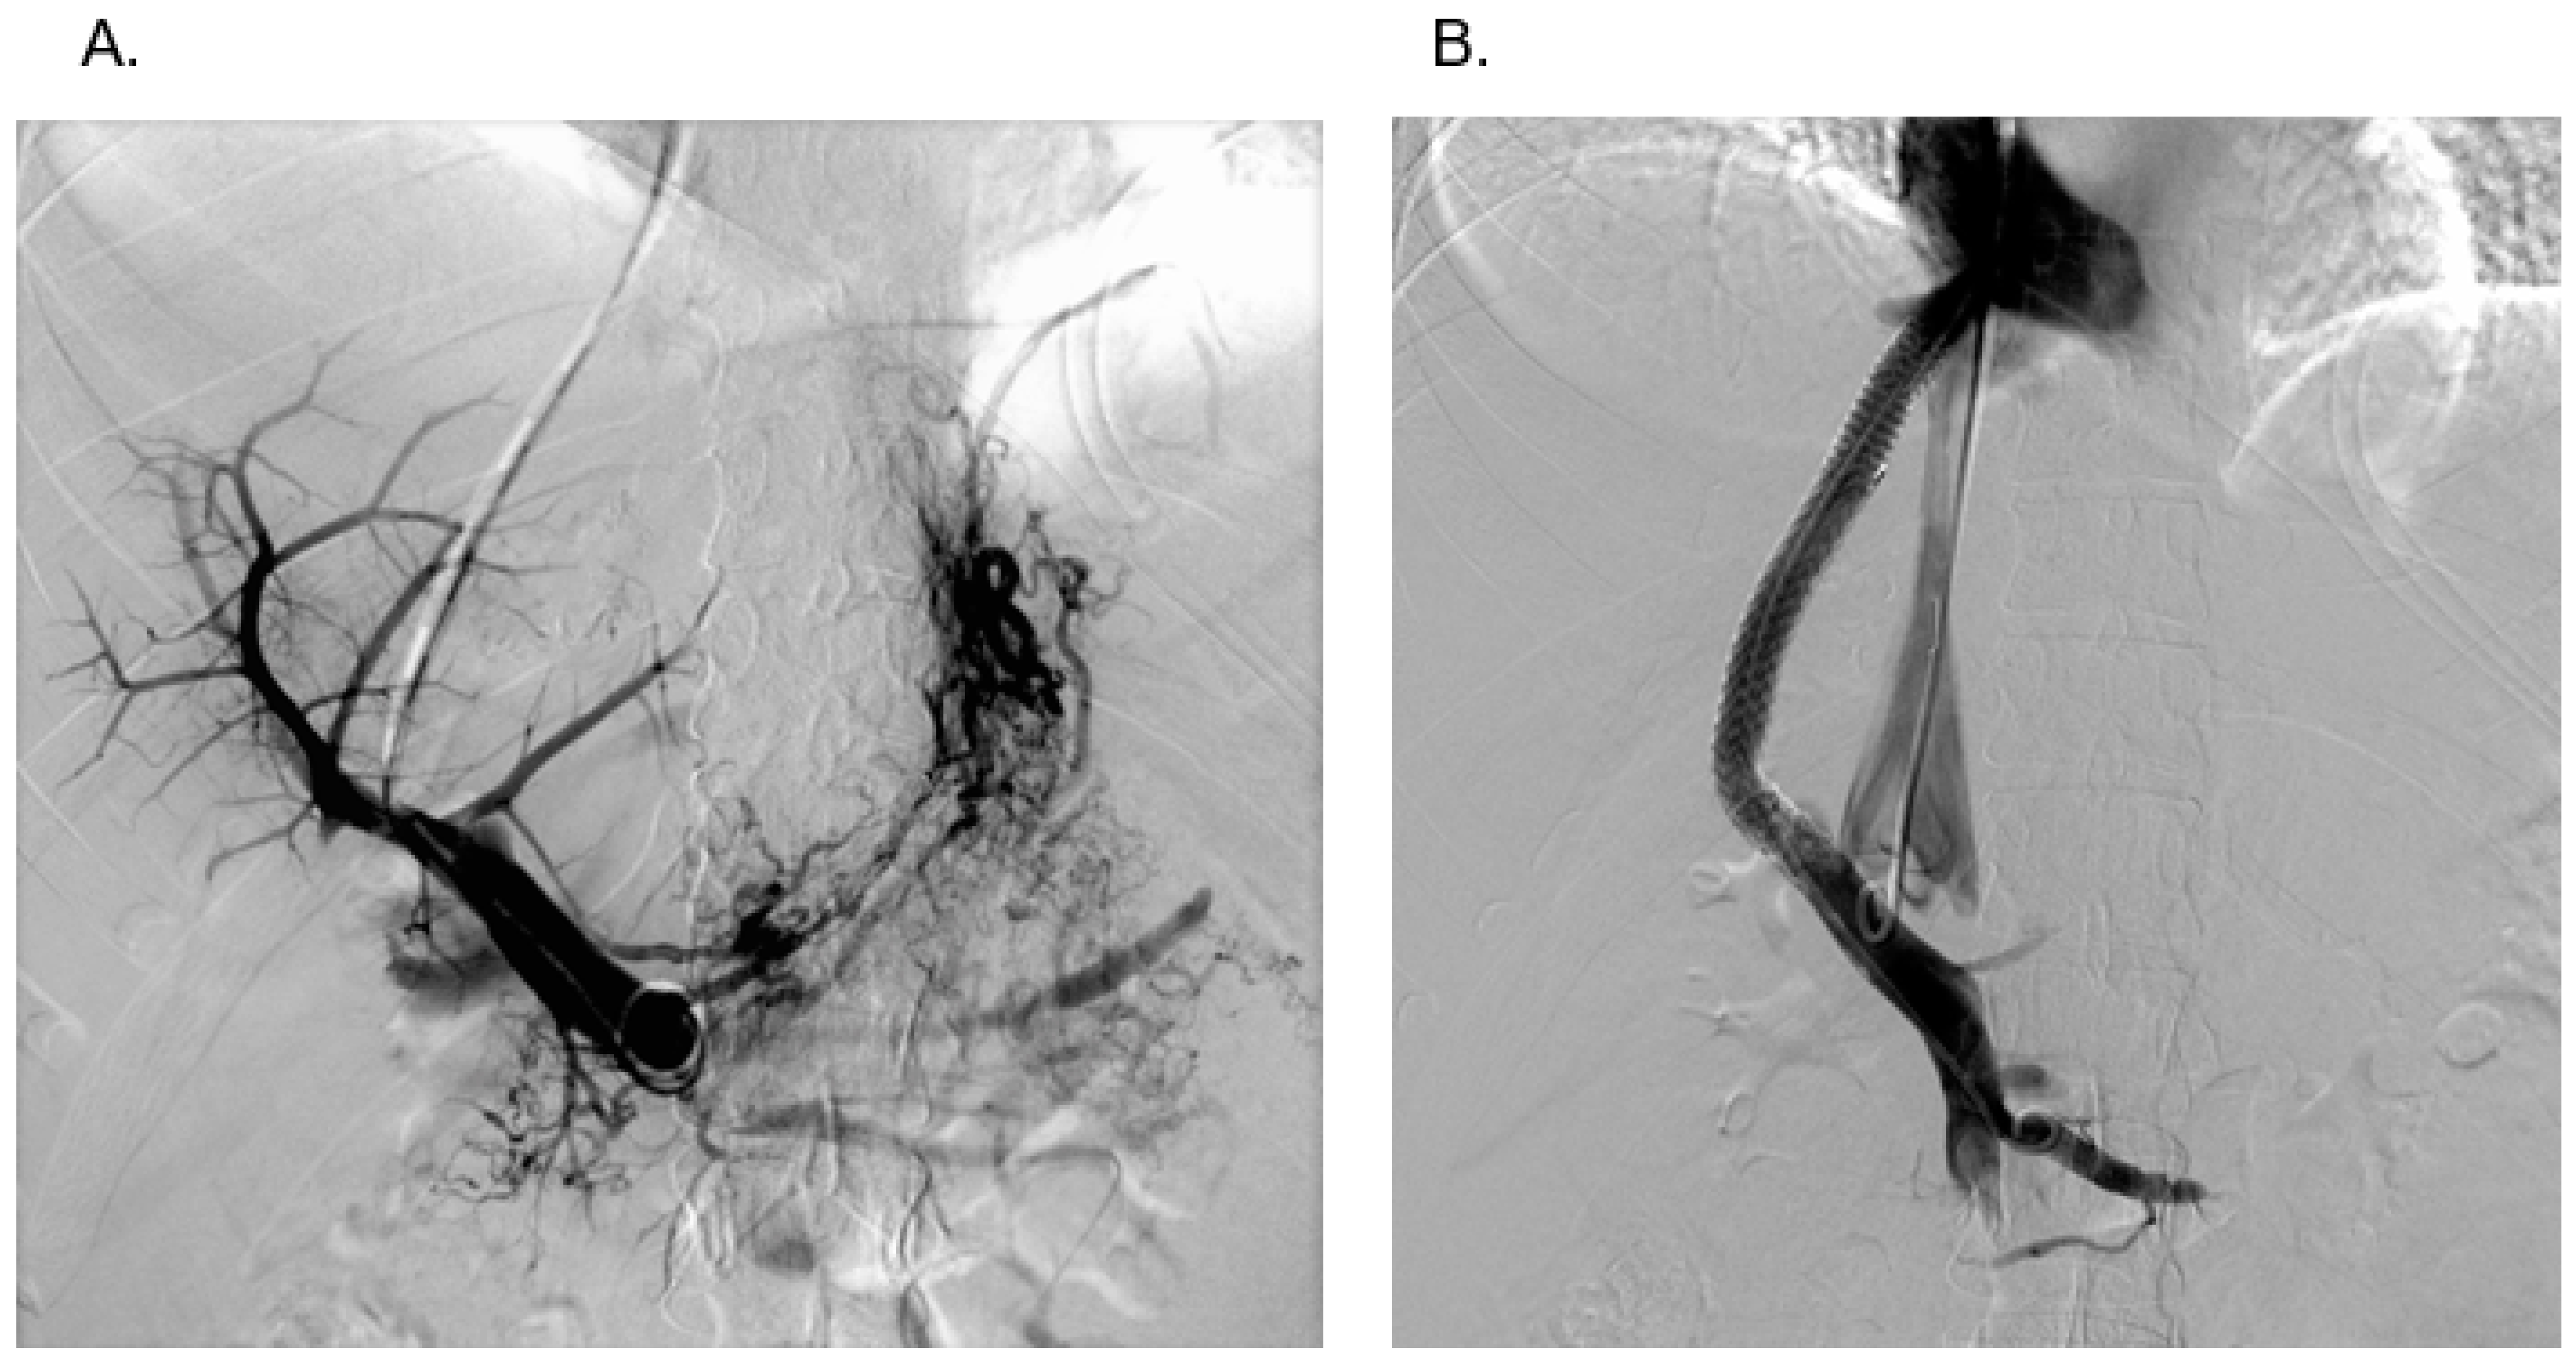

2.1. Angioplasty

2.1.2. Technique